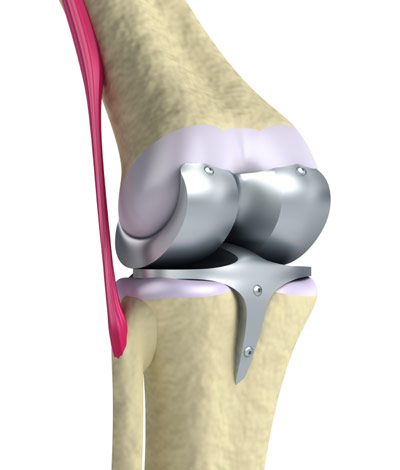

Zum Gelenkersatz gibt es mehrere Prothesenarten von verschiedenen Herstellern. Welche Möglichkeit gewählt wird, hängt von den individuellen Umständen ab, so unter anderem vom Zustand der Gelenkkapsel und der Bänder sowie vom Allgemeinzustand des Patienten. Meist wird eine Total-Endoprothese eingesetzt, bei der die gesamte Verbindung von Oberschenkelknochen und Schienbein erneuert wird (Knie-TEP). Nur manchmal genügt eine Teilprothese.

Die einfachste Art der Total-Endoprothese ist die Oberflächenprothese. Dabei werden die angegriffenen Gelenkflächen aus Knorpel vom Oberschenkelknochen und Schienbein zusammen mit einer dünnen darunterliegenden Knochenschicht abgetragen. Die freiliegenden Knochenflächen werden so bearbeitet, dass sich die Prothese genau einfügt. Diese wird dann an den beiden Knochen befestigt.

Falls auch die Gelenkfläche der Kniescheibe stark in Mitleidenschaft gezogen ist, kann diese zusätzlich ersetzt werden. Bisweilen muss das Kniescheibenband mitsamt einem kleinen Knochenanteil abgenommen und an veränderter Stelle wieder mit Schrauben befestigt werden, wenn es beispielsweise zu kurz ist.